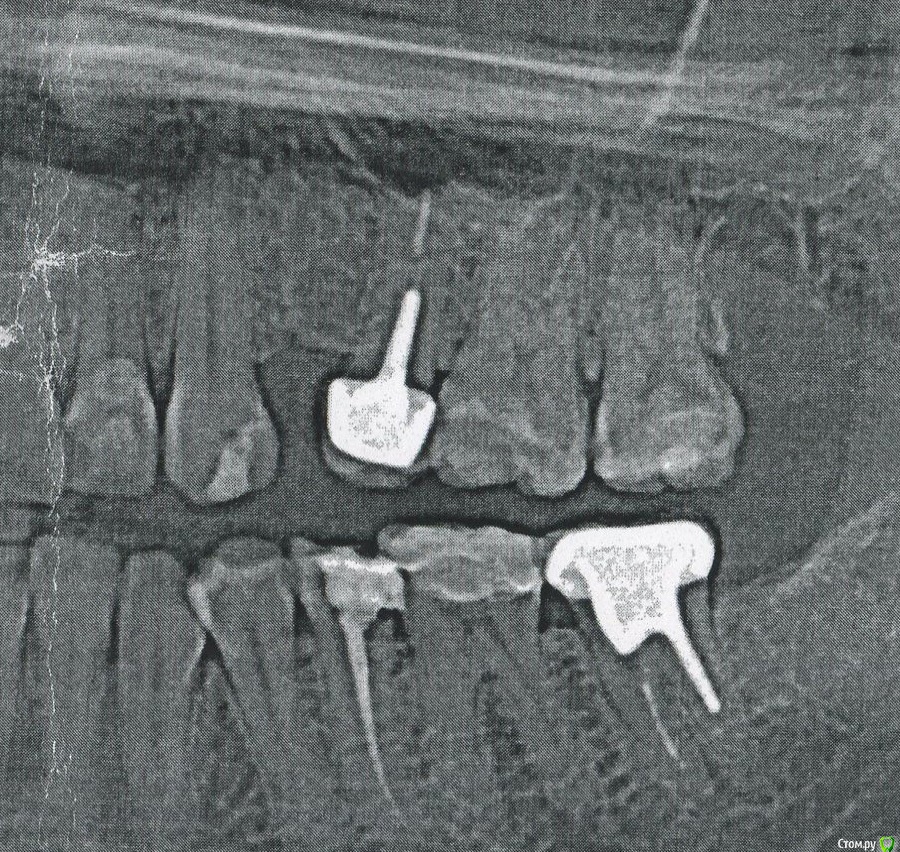

Jaz Опубликовано 17 сентября, 2017 Поделиться Опубликовано 17 сентября, 2017 (изменено) Здравствуйте! Расскажу всю историю по порядку и как можно более подробно2 месяца назад ужасно заболели зубы. Поехала в ночную клинику, там удалили зуб 28 (на котором еще и гранулема висела). Все успокоилось, я обрадовалась, хотя заживала лунка ужасно долго, и обезболивающие я пила постоянно. Через неделю после удаления восьмерки пошла на чистку.После чистки и ортопанорамы мне сообщили, что зубы 26 и 27 (рядом с удаленной восьмеркой) жутко разрушены и надо делать керамические вкладки. Это по словам врача поможет сохранить зубы живыми. Я спросила, нет ли там пульпита - я бы на фоне обезболивающего и удаления восьмерки просто бы не отразила пульпитные боли в этих зубах.Врач сказал, что пульпита нет. Я поверила.Приступили к лечению.Убрали все кариесы (5 часов в кресле, адские боли в процессе). Зубы удалось сохранить живыми. Сняли слепки, поставили временные пломбы. Через 4 дня - переделка слепков. Снова временные пломбы. Еще через 4 дня - снова переделка слепков и временные пломбы. И вот наконец вкладки установлены. Неприятные ощущения с временными пломбами были, но из-за повреждения десен неясно было, что именно болит. А вот после керамики место локализовалось. И тут возникла пугающая меня проблема. Зубы странно себя ведут. Они начали болеть через день после установки вкладок, появилось чувство распирания (в принципе нормально, там долго были просевшие пломбы). Тут же побежала к врачу. Врач осмотрел вкладки, сказал, что по высоте все нормально. Постучал по зубам и выдвинул предположение, что чувствительность связана с открытыми дентинными канальцами. Промазал все спецпастой. После этой пасты реакция на холодное (например, когда стоматолог воздухом сушил, я чуть ли не орала) снизилась, но не исчезла. Полдня ходила довольная, и вот снова: 1) в состоянии покоя все нормально, не болит. Просто чувство распирания и легкого зуда, неприятное такое почти болезненное ощущение (но не боль как таковая!)2) легкая ноющая боль при касании языка к зубам, проходит через несколько секунд 3) ноющая боль при касании холодного, от горячего ноет меньше. От теплой жидкости тоже ноет, если долго держать жидкость во рту4) сильнее всего болит, если касаться боковых стенок зуба ближе к деснам. И на стыке между 26 и 27 болит. Болит и сторона 27, примыкавшая к выдернутой уже восьмерке. 5) к ночи все эти ощущения усиливаются, но не перерастают в боль, при которой надо пить обезболивающие. Боль терпимая. Жевать могу, хотя чувствительность откровенно мешает. На стену не лезу, но это все равно пусть и слабая, но боль, и терпеть я не хочу. Врач уверен, что это просто повышенная чувствительность. Мол - живите так дальше, мы ничего не можем, только ждать. Что боль в течение недели после установки вкладки - это нормально. Я все же пошла и сделала по своей инициативе КТ. На КТ как сказал врач - расстояние между пульпой и вкладкой 1-1,5мм. И это значит (вероятность 50 на 50 по ее словам):1) все мои реакции вызваны воздействием вкладки и пройдут со временем, когда зубы "привыкнут"2) это пульпит, который лечащий врач не заметил, т.е. имеет место быть диагностическая врачебная ошибка. И это значит, что надо оба зуба депульпировать. Т.е. я потратила огромную сумму денег на бесполезное лечение, а на лечение пульпита денег уже и нет. Вопросы:Это пульпит или нет?Что мне сейчас надо делать? Ждать и надеяться, мазать зуб рем-гелем? Или идти со всеми данными к главврачу и требовать бесплатного лечения пульпита и установки коронок (ведь если это ошибка врача - они обязаны мне все передалать)? 1) Прилагаю ортопанораму ДО лечения. Я понимаю, что пульпит по панораме не определить, но можно понять, насколько обширный был кариес. Скажите, по такому снимку зубов 27 и 26 какое лечение вы бы назначили - депульпирование и коронку? Или как и мои врачи - восстановление керамической вкладкой на живые зубы? 2) Прилагаю снимок КТ после лечения, сделан сегодня (снимок 1 сегмента челюсти) - http://files.rentgen-online.ru/get.php?id=x8klsl6z5 заранее ОГРОМНОЕ спасибо! Изменено 17 сентября, 2017 пользователем Jaz Ссылка на комментарий